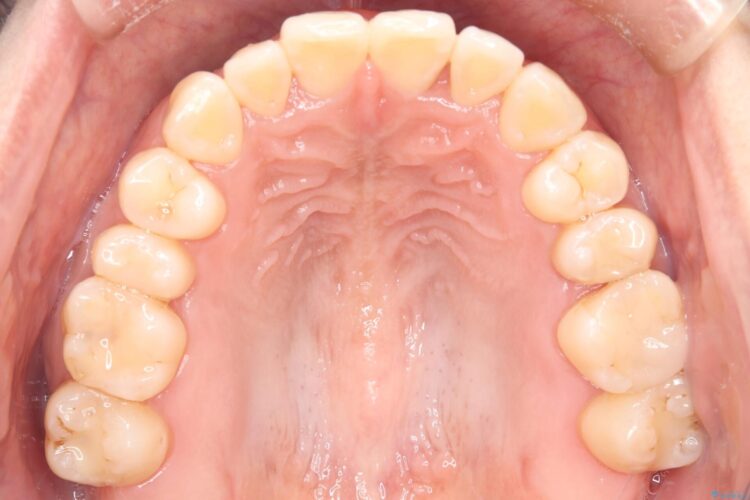

上の前歯のねじれが気になるとご来院された患者様です。

前歯の捻れとがたつきを改善するために、IPR(歯と歯の間を削る処置)と歯列拡大をすることで歯並びを整えていく治療計画を立てました。